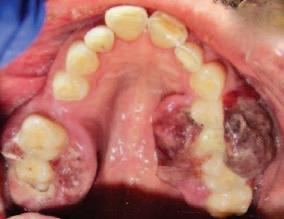

A 30-year-old patient presented to your clinic complaining of a discoloured front tooth (Figures 1 and 2). There was no pain or other symptoms associated with it and it has become increasingly discoloured over time.

1. What is the likely reason for this type of discolouration?

2. What special tests do you perform as part of your exam?

3. What are the potential sequalae for this tooth?

4. What are the possible treatment options for

this tooth and what are the potential difficulties with doing a root canal treatment?

Answers on page 45.

FIGURE 1: Patient presenting with discoloured front tooth. FIGURE 2: Periapical radiograph 1.